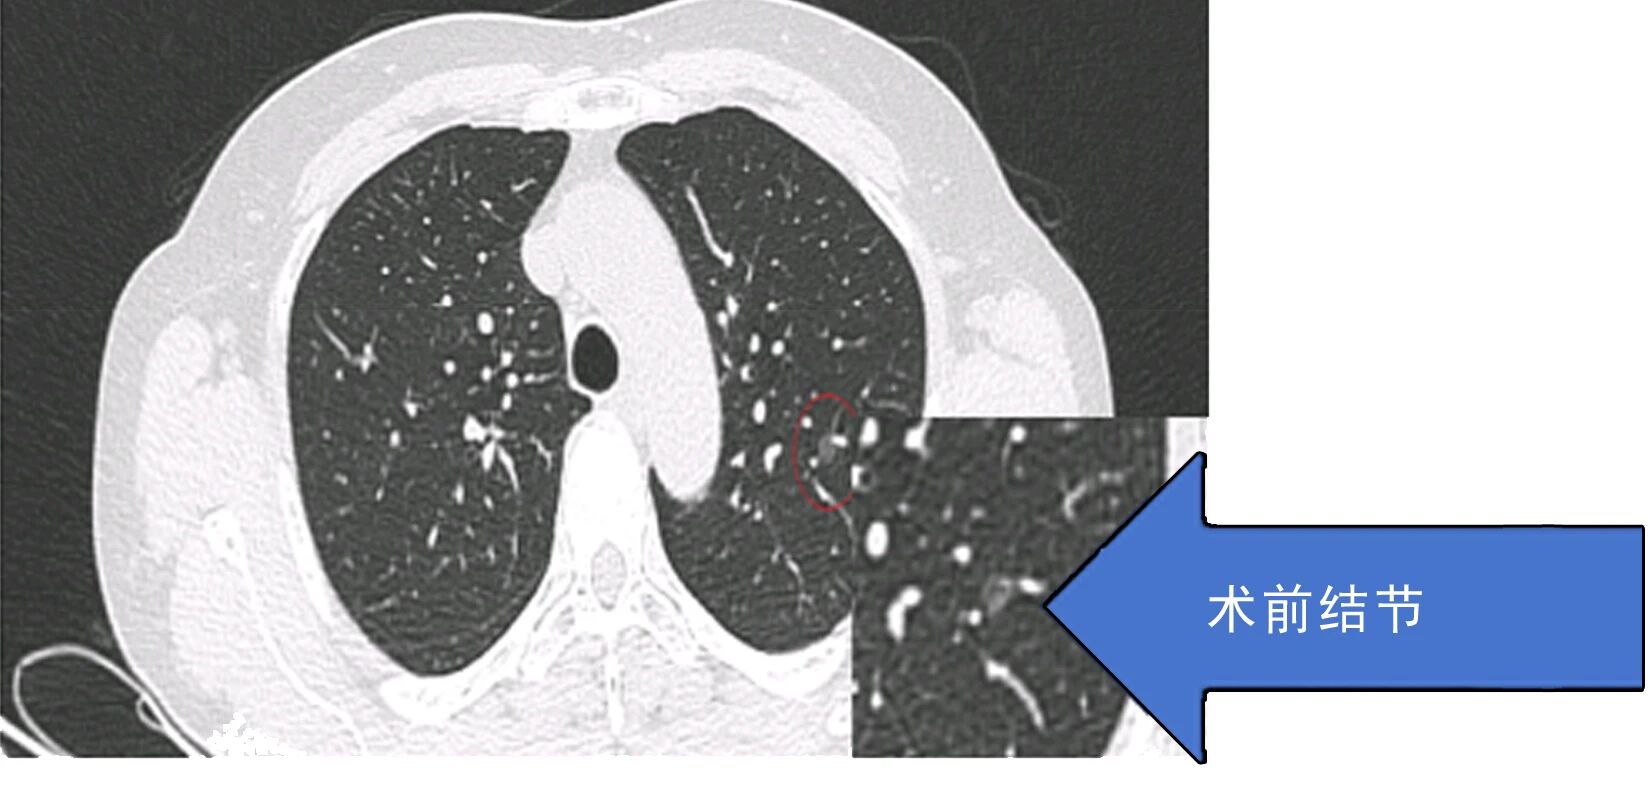

患者因肺结节就诊后,术前检查提示传统手术可能造成较大肺功能损伤,患者及家属因此产生明显焦虑情绪。胸外科团队综合评估病情后,决定采用微波消融技术施治。手术依托CT实时导航技术,将消融针精准送达结节部位,误差控制在3毫米以内,仅通过一个针孔创口完成操作,单次消融过程耗时5-10分钟,患者3天内出院,健康肺组织功能得以保留。